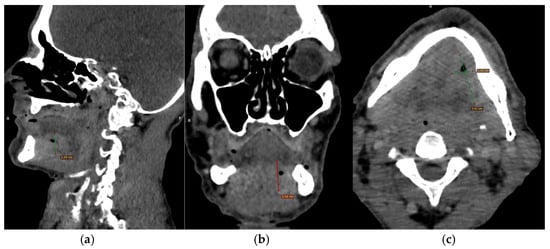

CECT of the oral and submandibular region revealed a heterodense lesion within the left sublingual space, measuring approximately 34 × 13 × 20 mm, with a depth of 18 mm (Figure 3). The lesion exhibited fluid content with small central air inclusions and peripheral contrast enhancement, without evidence of adjacent osseous destruction (Figure 4).

Figure 3.

(a–c) CECT images (a) Axial section showing a heterodense lesion in the left sublingual space with central necrosis and peripheral enhancement. (b) Coronal section demonstrating the lesion confined to the left side without crossing the midline. (c) Sagittal section illustrating the depth of infiltration (18 mm) without evidence of mandibular bone involvement.